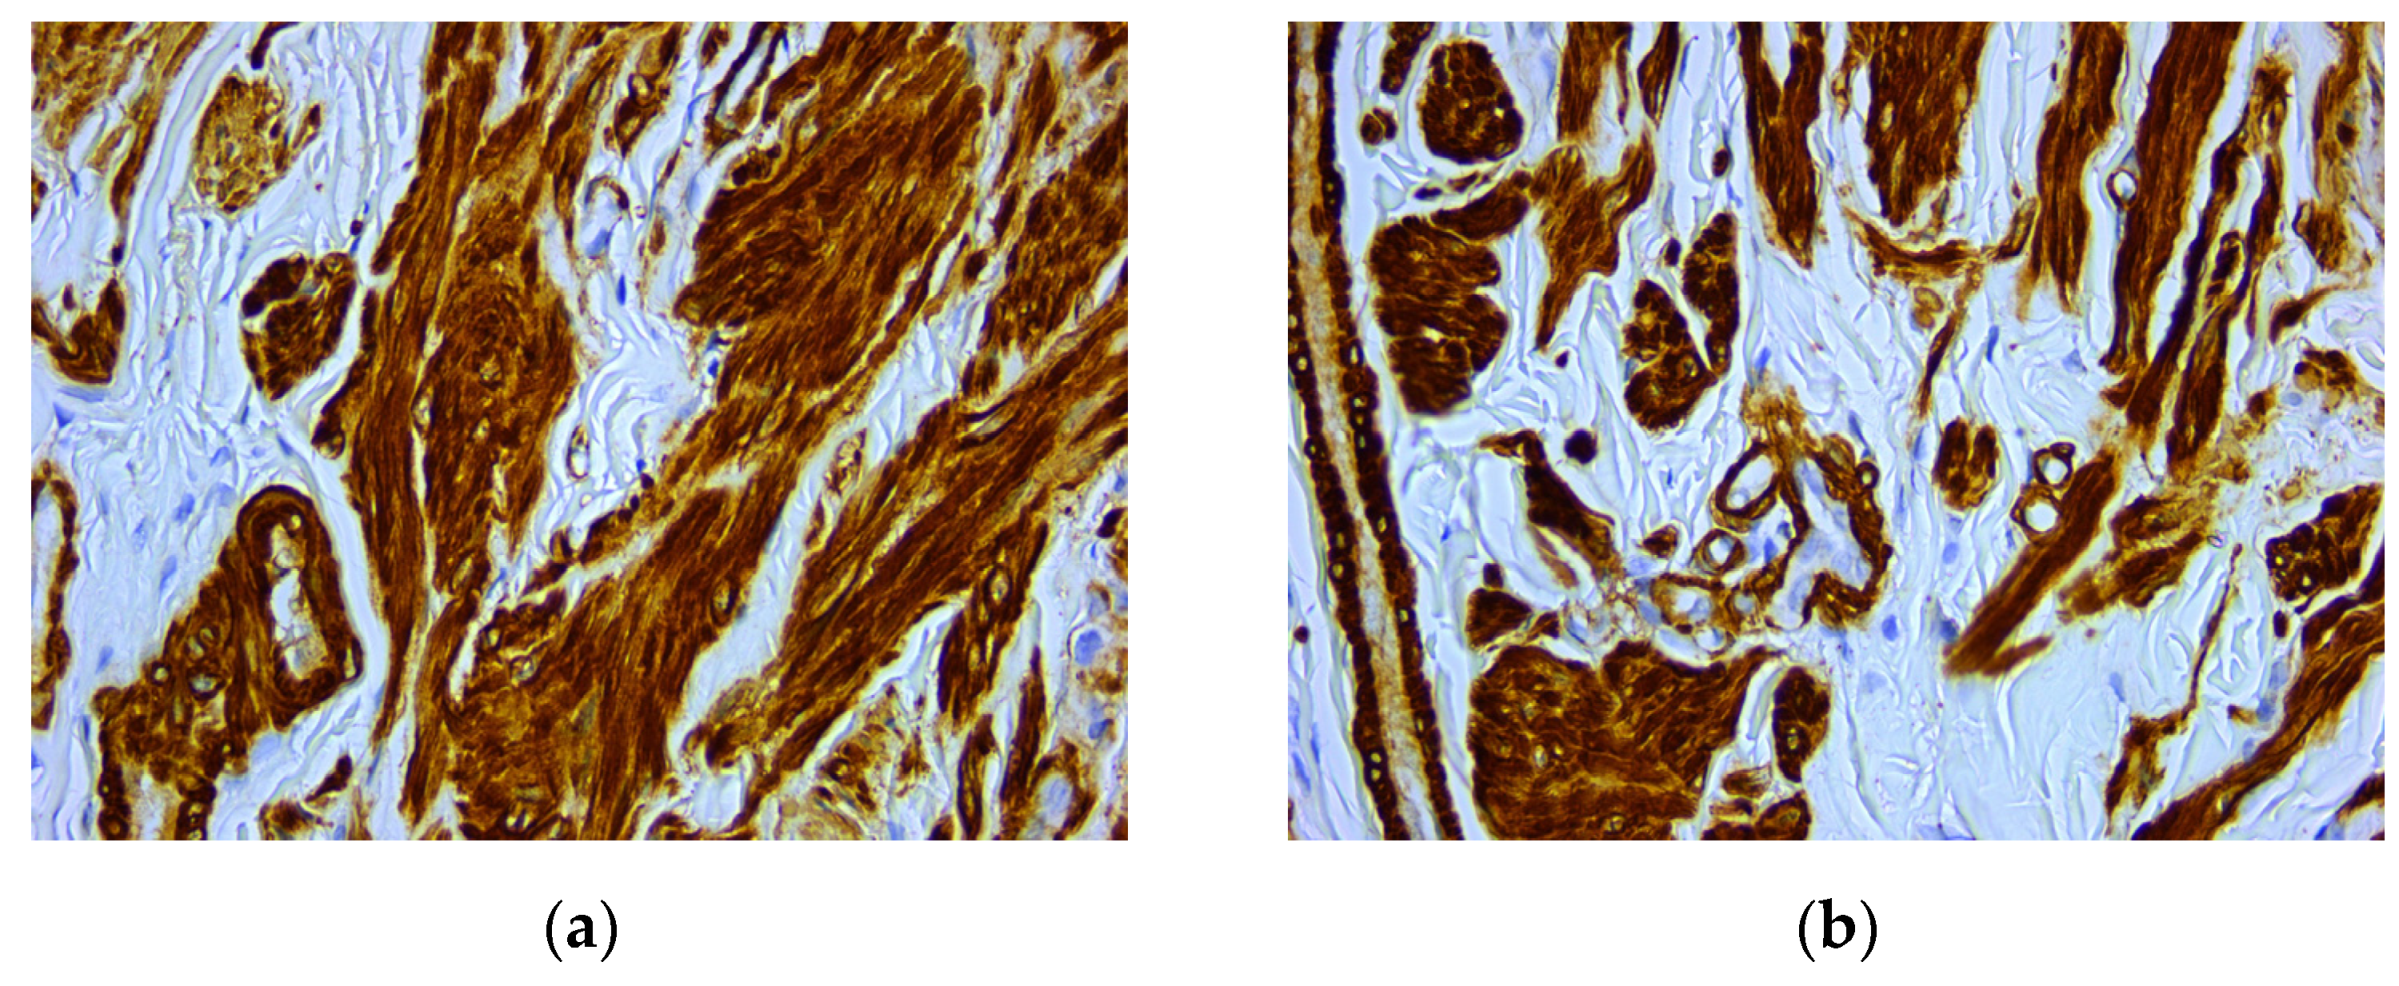

An intense and diffuse positive immunohistochemical reaction in all the tumor cells was found for desmin with a cytoplasmic pattern (Figure 4). In addition, smooth muscle actin was intensely positive in all the tumor cells with a cytoplasmic and nuclear pattern of distribution (Figure 5). On the other hand, vimentin was negative, with positive internal control at the level of the connective tissue (Figure 6). The Ki67 cell proliferation index was 3%, with only a few tumor cells being positive (Figure 7).

Figure 5. Microscopic images of IHC reactions for smooth muscle actin, ob. 40x: (a) intense and diffuse positive reaction in all tumor cells; (b) positive reaction with cytoplasmic distribution.